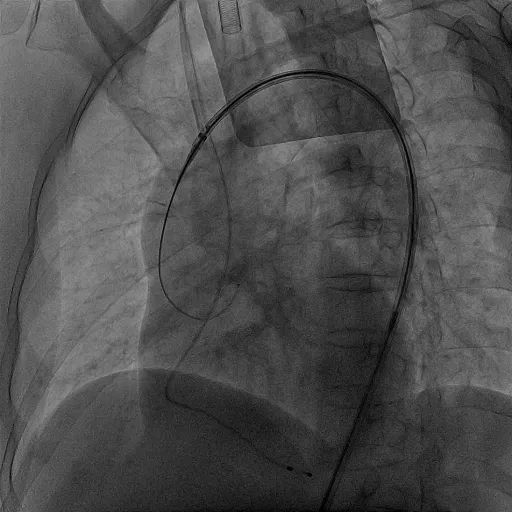

晋军主任团队在手术中,克服了横位心和扭曲主动脉等难题,为患者植入一枚VenusA-Valve® L23型号的人工主动脉瓣膜。人工主动脉瓣置入后,病人人工主动脉瓣口收缩期峰值血流速度150cm/s,峰值压差9mmHg,平均压差3mmHg。

介入瓣膜释放位置非常满意,血流动力学效果非常好。

TriGUARD3™下释放瓣膜